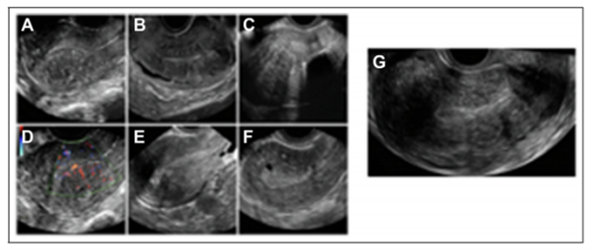

图1.A)子宫后肌层不对称增厚;B)交界区不规则增厚,有异位子宫内膜小回声区;C)扇形阴影,有原位宫内节育器;D)病灶区血管分布,血管垂直于子宫内膜;E)子宫内膜下芽状回声;F)前子宫腺肌症伴肌层囊性病变;G)子宫球形增大。